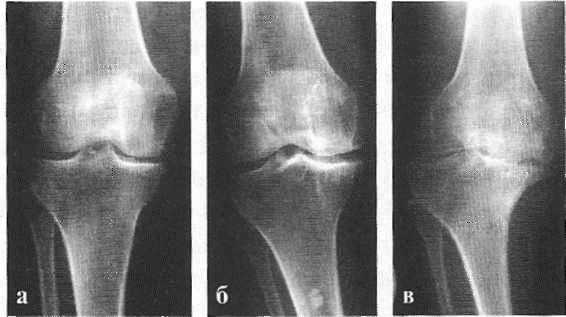

В подавляющем большинстве случаев достаточно осмотра и рентгенограммы коленного сустава в двух проекциях (прямой и боковой). [2] [19] Клинические данные и снимки позволяют определить стадию заболевания.

На ранних стадиях заболевания, при незначительных изменениях в костной ткани, рентгенологическое обследование не настолько ценно. [5] [8] На этом этапе гонартроз возможно диагностировать благодаря артроскопии. [5] [8] Точность метода очень высока, останавливать может только его инвазивный характер и цена.

Может протекать бессимптомно, иногда появляются умеренные боли после физических нагрузок, быстро исчезающие в покое. Рентгенография: изменения отсутствуют или имеется небольшое сужение суставной щели. МРТ на 1 стадии коксартроза: в хрящевой ткани появляются признаки неоднородности.

2 степень артроза тазобедренного сустава

Боли усиливаются, иррадиируют в колено, голень и голеностоп, в покое проходят не сразу. Рентген: явное сужение суставной щели и единичные разрастание костной ткани (остеофиты) по краю суставной впадины. МРТ на 2 стадии коксартроза: явные дефекты (эрозии, трещины) хряща с утратой менее половины объема хрящевой суставной ткани.

3 степень артроза тазобедренного сустава

Ногу трудно отводить в сторону и поворачивать внутрь, боли усиливаются, часто появляются в покое во сне. Болезненность в ноге при ходьбе заставляет принимать вынужденное положение тела и опираться на трость. Рентген: суставная щель еще более суживается, множество остеофитов приводит к деформации ТБС. МРТ на 3 стадии коксартроза: разрушено более половины объема хрящевой ткани. Третью стадию еще можно лечить консервативно.

4 степень артроза тазобедренного сустава

Значительная утрата суставной функции. Болит вся нога: область ТБС, пах, ягодичная область, бедро, колено, голеностоп. Развивается плоскостопие, нога укорачивается, мышцы атрофируются. Рентген: множественные крупные остеофиты, суставная щель сужена до минимума или отсутствует. МРТ на 4 стадии коксартроза: хряща нет, появляются изменения в костной подхрящевой ткани в виде уплотнения (склероза).